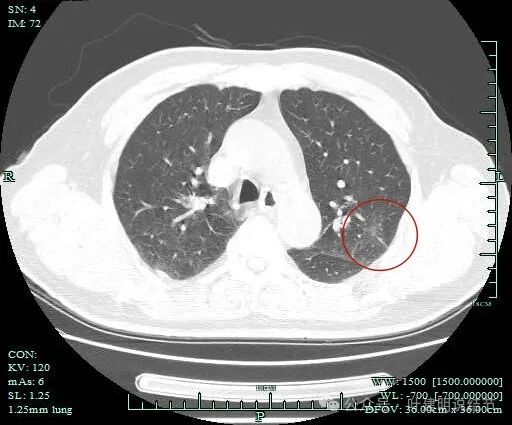

明显血管穿行于灶内。

病灶距斜裂与胸肋面的胸膜都近。